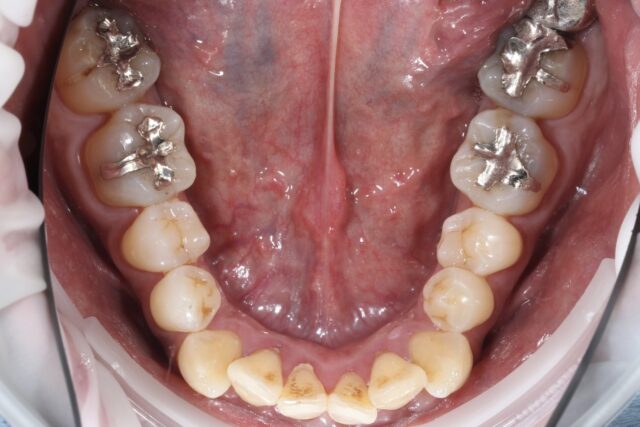

before

after